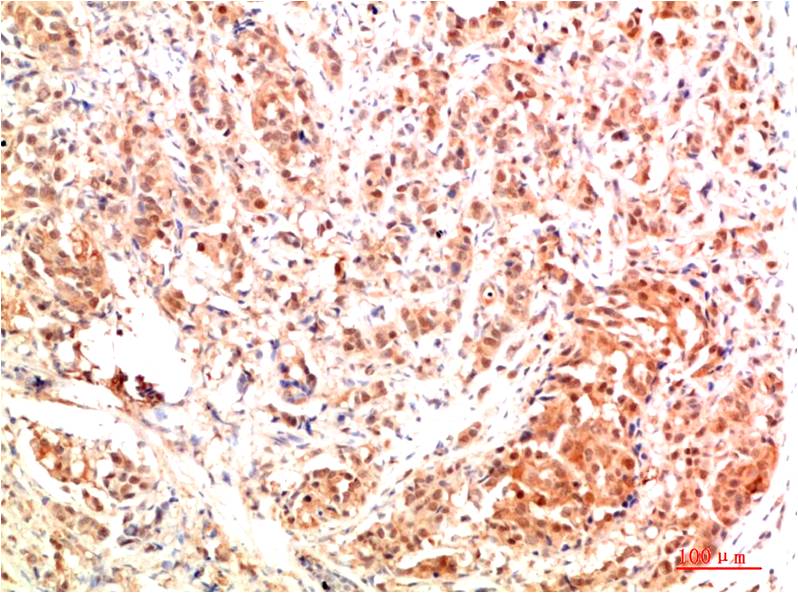

c-Jun Mouse Monoclonal Antibody(4G10)

Applications :IHC

| Recommended dilutions: | IHC 1:100-200 |

| Specificity: | The c-Jun Mouse Monoclonal Antibody can detects endogenous c-Jun proteins. |